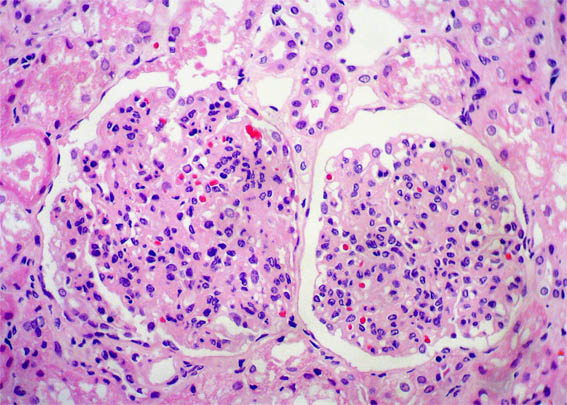

Figura 2.

H&E, X200.